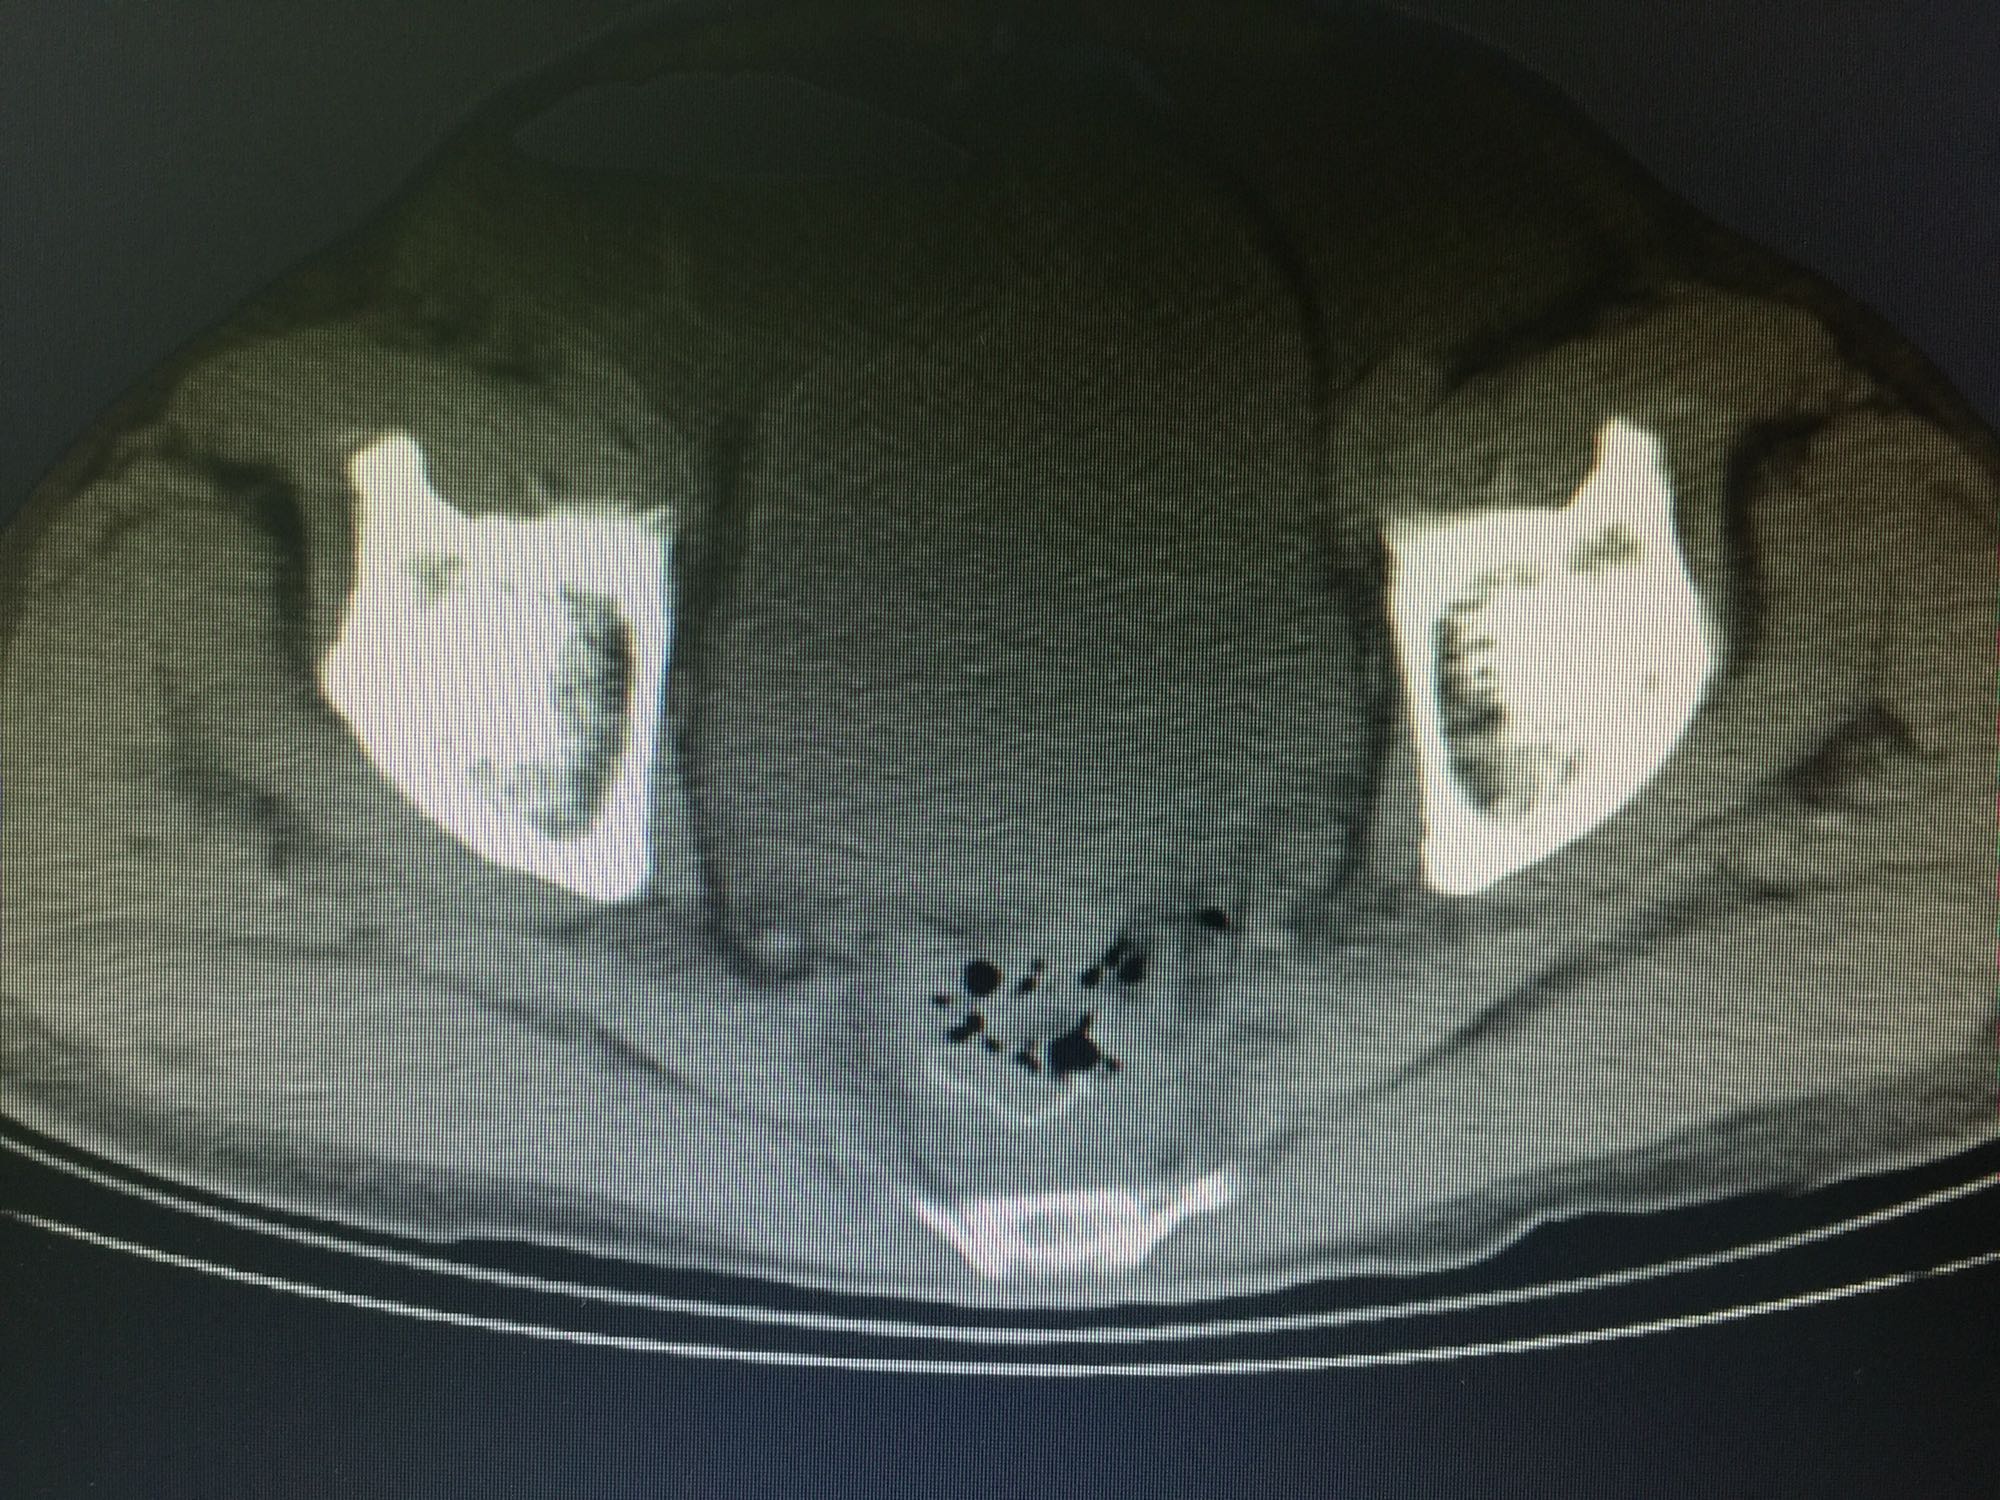

诊断:直肠癌,结肠息肉。 治疗:直肠低位前切除术,术后7天盆腔引流量逐渐增多,伴腹痛、发热,血像明显增高,腹部CT见腹腔大量积液,吻合口处结构不清晰,直肠旁间隙见条索状增强影;再次手术证实为吻合口漏。